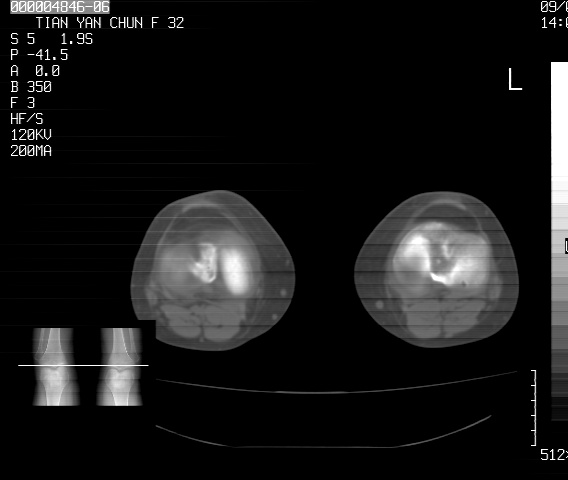

标题: CT18487:请会诊,女32岁,左膝疼痛数日 [打印本页]

标题: CT18487:请会诊,女32岁,左膝疼痛数日

关节面软骨有硬化环考虑退行性变

定位片可见髁间棘骨质增生,支持膝关节退行性变。

定位片可见髁间棘骨质增生,支持膝关节退行性变。建议mri 检查

考虑骨性关节炎